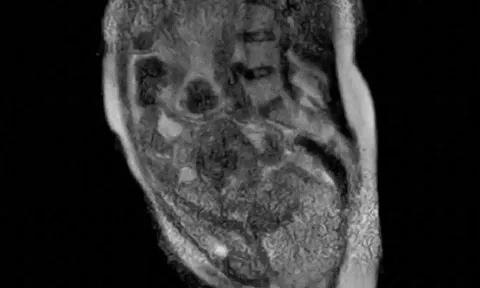

Người đàn ông 50 tuổi suy thận, phải chạy thận suốt đời vì uống cà phê kiểu này mỗi ngày- Ảnh 1.

Kết quả kiểm tra cho thấy mức lọc cầu thận ước tính (eGFR) đã tụt xuống dưới 10, tương đương suy thận mạn giai đoạn 5. Điều đáng nói là bệnh nhân không hề mắc đái tháo đường, tăng huyết áp hay gout, những nguyên nhân phổ biến dẫn đến suy thận. Sau khi loại trừ nhiều yếu tố, bác sĩ cuối cùng phát hiện thủ phạm chính là thói quen sử dụng cà phê hạt đã ẩm mốc, biến chất trong thời gian dài.